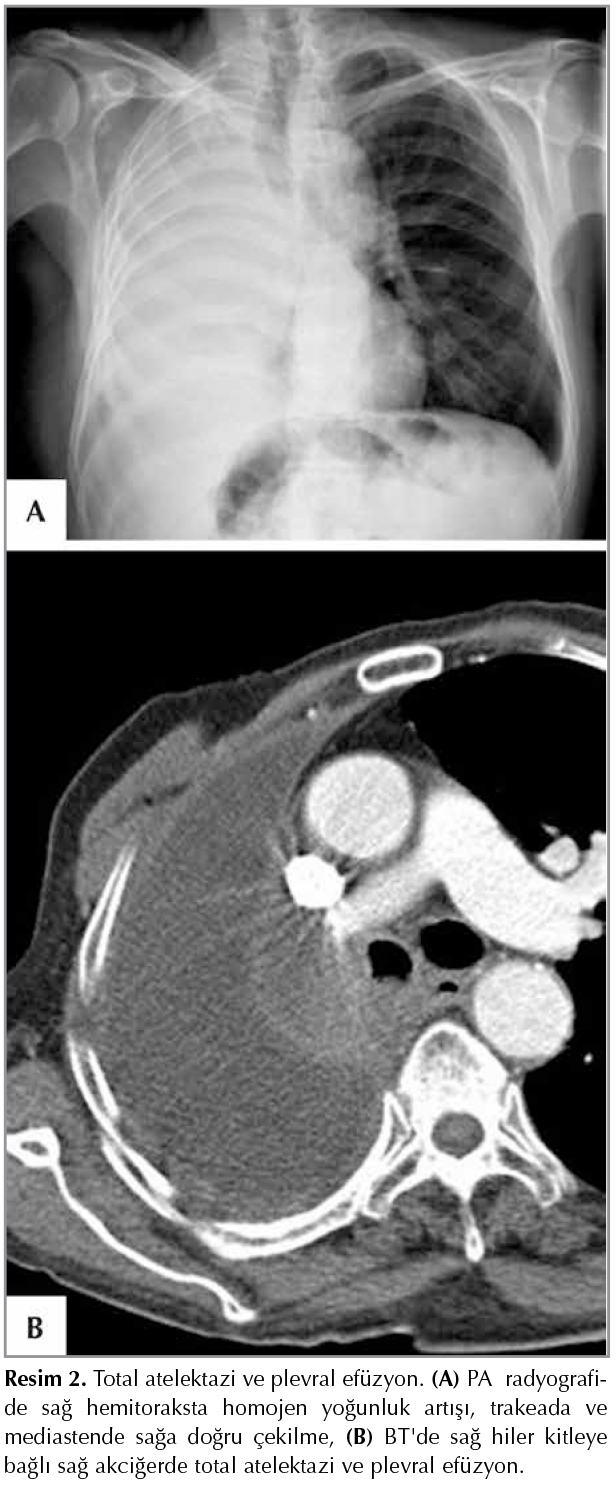

Vertikal pozisyondaki olguda plevral sıvı akciğerin alt y?zeyi ile diyafragma arasında toplanır. Plevral boşluktaki sıvı 75 mL'den az ise diyafragma ve kostofrenik sin?sler normal morfolojik yapıdadır. PA akciğer grafisi sıvının olduğunu g?stermeyebilir. Sıvı belirli miktara ulaşınca ?nce posterior, sonra lateral kostofrenik sin?ste kapanma g?r?l?r. Lateral kostofrenik sin?s?n kapanması i?in plevral sıvı en az 175 mL olmalıdır. Posterior kostofrenik sin?s lateral kostofrenik sin?sten daha derin olduğu i?in az miktardaki sıvı yan radyografide posterior kostofrenik sin?s?n kapalı olmasına neden olmaktadır (4-6). Plevral boşluktaki sıvı arttık?a etkilenen diyafragma yaprağı ve sin?slerin konturu silinir. Sıvı anterior, lateral ve posterior toraks duvarı boyunca plevral boşluğu doldurur. Mediastinal plevral boşluğa ise sıvının bir miktarı ge?ebilir. ??nk? akciğerin mediastinal y?zeyi hilus ve pulmoner ligament d?zeyinde fiksedir. Plevral boşluktaki sıvının belirli miktara ulaşması ile PA ve yan radyografilerde a?ıklığı yukarıya bakan yoğunluk artışı parabolik eğri konfig?rasyonu g?stermektedir (Resim 1). Plevral boşluktaki sıvı hastanın pozisyonunun değişmesiyle yer değiştirebilir (serbest plevral sıvı). Masif plevral sıvıya rağmen mediastende karşı tarafa itilme yoksa akciğerde atelektazi veya kollapsın bulunduğunun işaretidir. Bu bulgu bronş kanserinde g?r?lmektedir (Resim 2) (7).

Resim 2